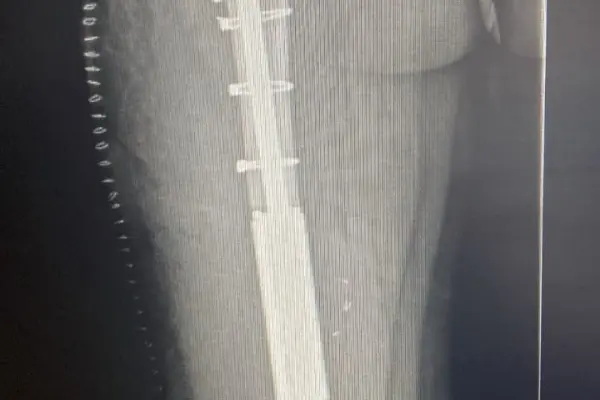

V létě 2023 jsem začala trpět bolestmi zad. Na jaře mi snížili invalidní důchod, takže jsem v kavárně již pracovala. Myslela jsem, že je to tím - víc pohybu, jiný režim,… Postupně ale přicházely dny, kdy jsem sotva vstala z postele. Klidové bolesti, které jsem už dobře znala. Podvědomě jsem tušila, ale přiznat si to bylo moc těžký. Kontrola v srpnu mé nejhorší obavy potvrdila. Metastáza v páteři. Byla to asi největší beznaděj, jakou jsem dosud cítila. Hlavou se mi honilo, že už se s Enie neprojdu a jak mi bude naše toulání chybět. Na kontrolní celotělové scintigrafii před operací se odhalila ještě jedna metastáza. Ve stehenní kosti. Následovalo čekání na rozhodnutí spondylochirurgů, jestli budou vůbec operovat. Věděla jsem, že pokud do toho nepůjdou, nečeká už mě pěkná cesta. Mezitím ortopedi rozhodli, že stehno odoperují zhruba měsíc po operaci páteře, pokud se uskuteční. A i když Brno nemám od začátku zrovna v lásce, musím říct, že lepší doktory bych si snad ani nemohla přát. A tak jsem 1. září v půl sedmé ráno usínala na operačním sále a jen doufala, že se operace podaří. Probrala jsem se po páté odpoledne na JIP a upřímně, nezažila jsem větší bolest. Byl mi nahrazen obratel a stabilizace sahá přes další čtyřiobratle. Tři týdny v bolestech, ale ten čtvrtý jako zázrakem bylo po. Bez bolestí jsem se s Jirkou a Enie vydávala denně na procházky, abych si každou chvíli s nima venku užila naplno. Protože 5. října už jsem ležela na operačním sále znovu. Tahle operace nebolela ani zdaleka tolik jako ta předchozí, co ale bolelo byl následující rok o berlích. Od listopadu jsem ještě podstoupila ozařování páteře, protože histologie nepotvrdila čisté resekční okraje. A následně jsem denně začala užívat udržovací chemoterapii v tabletách. Další kontroly v roce 2024 vycházely krásně, čistě. V hlavě jsem ale stále bojovala s berlemi. Ale měsíce utíkaly.